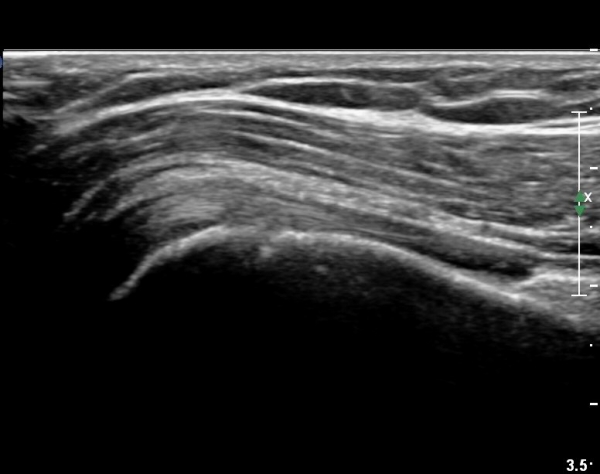

ÃÊÀ½ÆÄ °Ë»ç

´ë°áÀý°ú °ßºÀÇϺο¡ ¹æ»ç¼± Åõ°ú¼º °¨¼Ò(sclerosis)°¡ °üÂûµÈ´Ù(÷ºÎÆÄÀÏ).